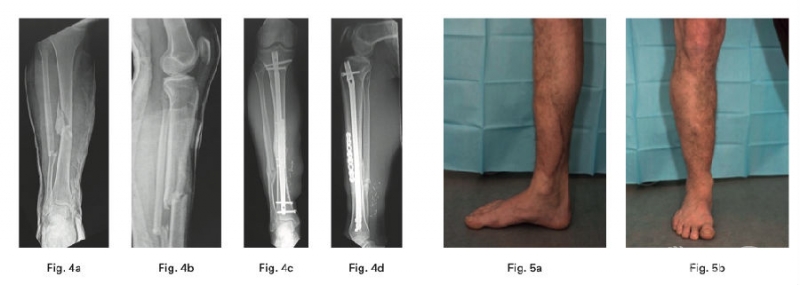

胫骨平台骨折是过去二十年研究的热点,从分型到治疗有了成熟的研究和认识。而小腿骨折和足踝部骨折因大量的手术病例和并发症,始终是研究的一个热点。

2、Hourani AI在一项病例系列中确定了使用mechanically relevant devitalized bone (ORDB)进行矫形重建是否与IIIB型开放性胫骨干骨折感染率增加相关,其结论为在IIIB型开放性胫骨干骨折治疗的情况下,在最终重建中使用ORDB是安全的。